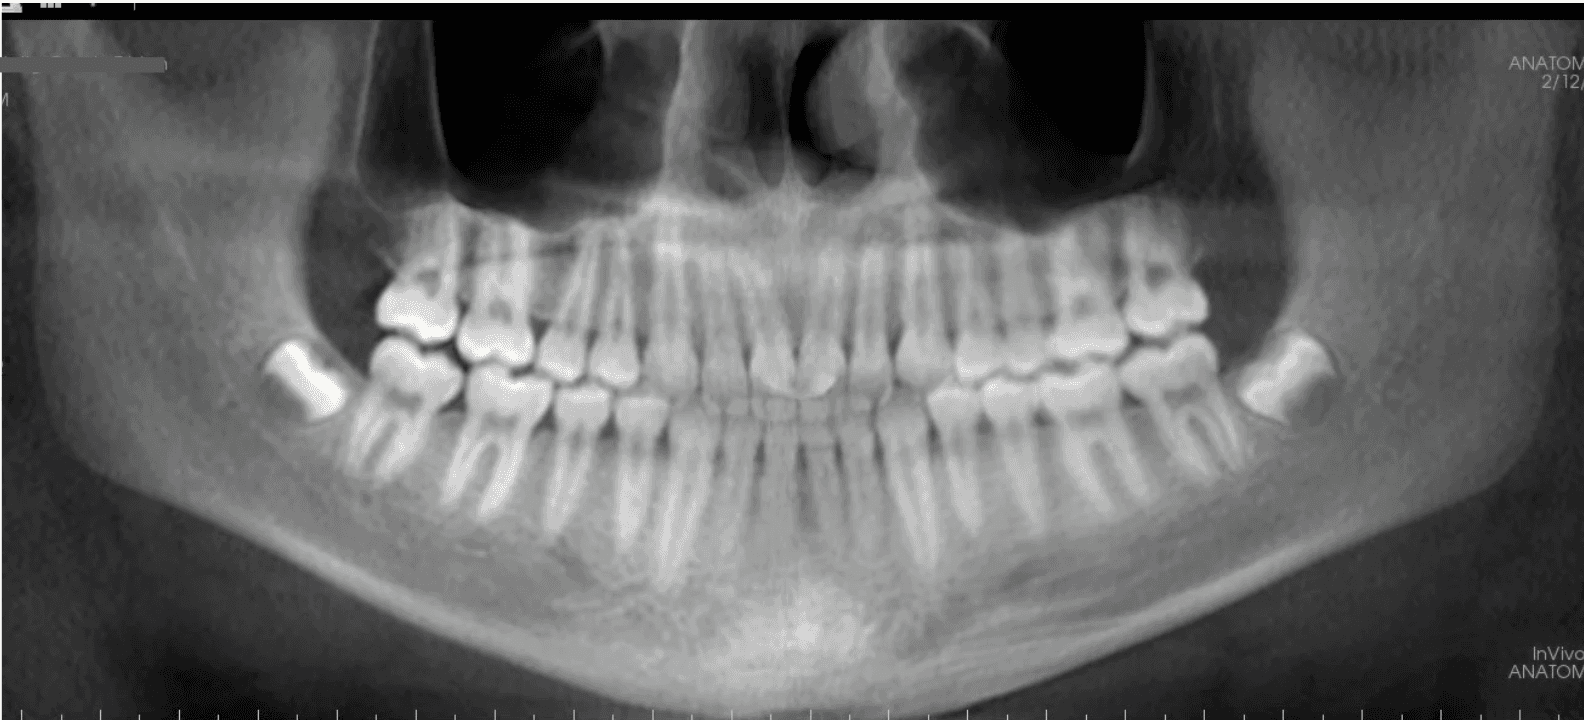

Initial treatment

X-RAYS